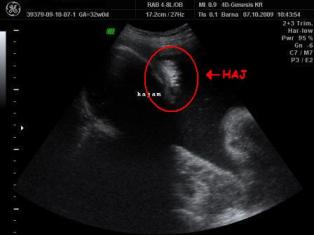

Minden rendben lurkóval, valóban fejvégű, 2100 gr. Kissé nagyobb lesz, mint Bátyja. Megint szóba jött a doki-dolog, hát eléggé meglepődött, amikor mondtam, hogy valószínűleg a dokim nézte el a gyerek fekvését (26. héten faros volt, utána éreztem egy fordulást -egyértelműen-, 30. héten mégis farosnak mondta a doki, azaóta nem éreztem fordulást és most viszont fejvégű (meg ugye előző héten is az volt) ergo szerintem a doki nézte el. No a lényeg, hogy megint beszéltünk erről, de mondtam Neki, hogy már nem akarok nagyon ugrálni... Amúgy a szülésznőmnek mondta, hogy majd együtt szülnek és hogy én leszek az... jééé emlékszik... És lenne mégegy téma ezzel kapcsolatban, de azt nem merem itt nyíltan...